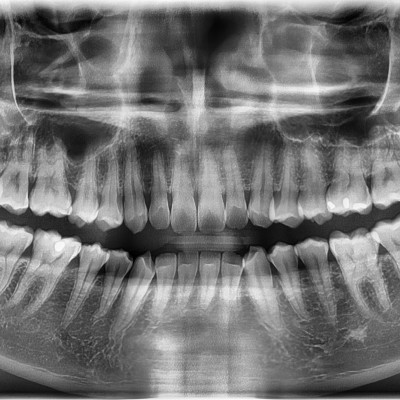

#18사랑니 발치 + #19 과잉치발치 #18사랑니 발치 + #19 과잉치발치 구강 외과 전문의가 당일 발치했습니다. ---------------..

작성자 이턱이 작성일 02-10 조회 51